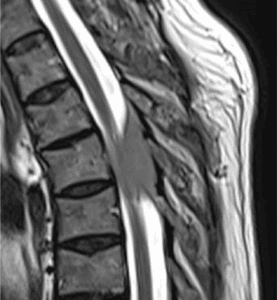

Meningioma dorsal intra raquideo

Masculino, 72.

Lumbalgia de un año de evolución, constante, no mecánica, con mala respuesta al tratamiento médico.